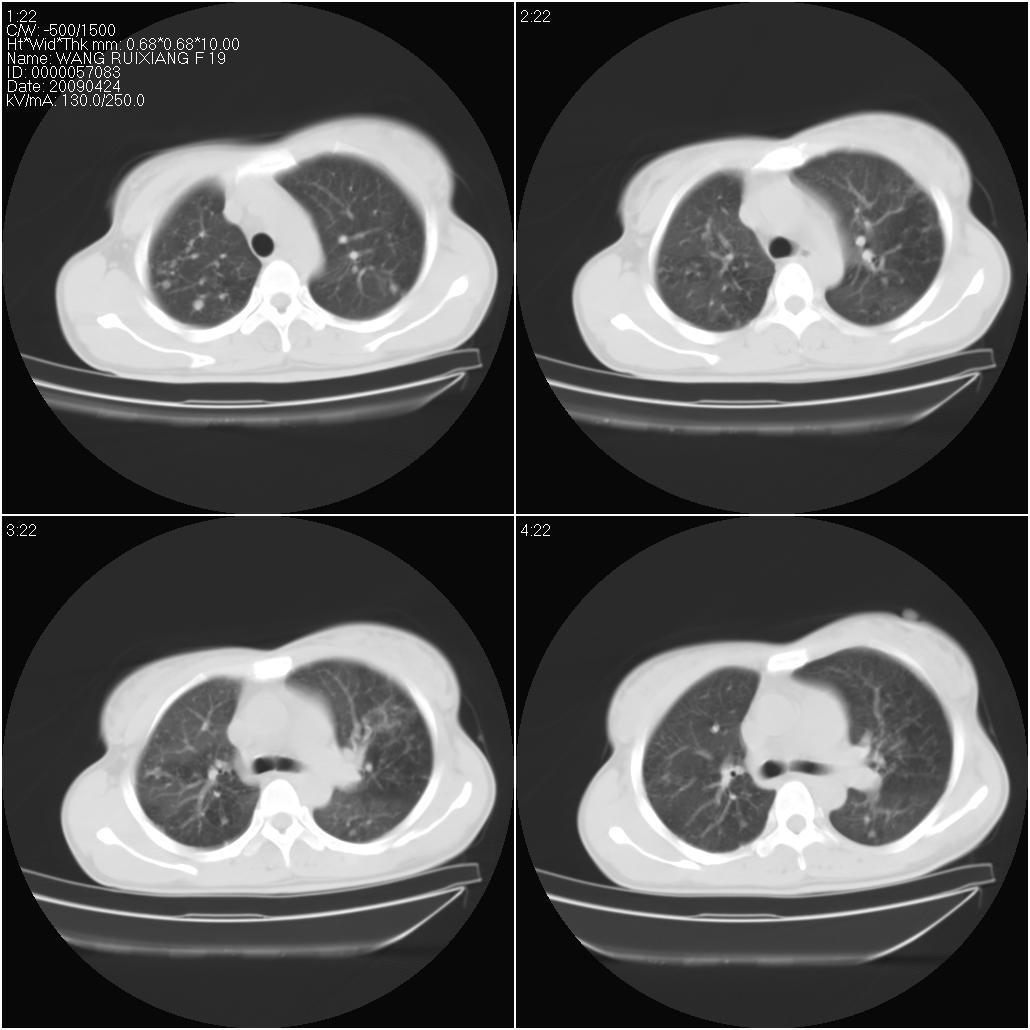

标题: CT19588:女性,39岁。患者胸闷不适,上楼时气喘。 [打印本页]

标题: CT19588:女性,39岁。患者胸闷不适,上楼时气喘。

片子上的年龄为19岁,是操作错误。该患者于去年5月份曾做平片和ct扫描,和这一次的ct检查没有明显变化。当时诊断为肺结核,进行抗痨治疗至今,但没有改善。呼吸功能试验为混合型呼吸困难。除此之外,该患者没有其他方面没有的临床症状和体征

两肺见斑点片状阴影,部分病灶密度较高,右下肺见小囊状及柱状蜂窝状阴形,考虑为两肺结核以阵旧性为主,右下肺支扩。

1)两肺继发性肺结核(以增殖病灶为主)。2)两肺下叶支气管扩张。